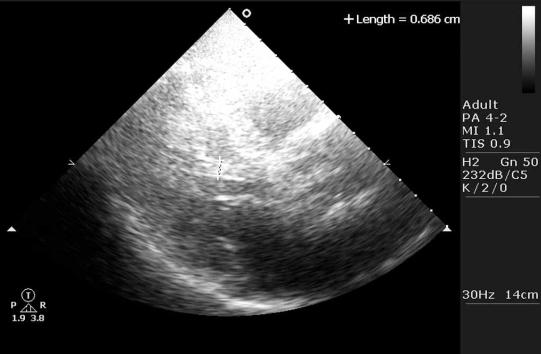

Right bundle branch block is an electrocardiographic phenomenon with specific criteria.Currently, two specific forms of right bundle branch block are acknowledged, a proximal and a distal variant. A vast array of pathologies can cause proximal, distal or even combined forms of right bundle branch block.IN THIS STUDY IT IS SUGGESTED THAT A THIRD TYPE OF RIGHT BUNDLE BRANCH BLOCK EXIST: one caused by a subaortic muscular tendon in the left ventricle, leading to an increased velocity of conduction in the left ventricle, with a resultant "relative" right bundle branch block. It is concluded that it is necessary (and time) to take a closer look at endoventricular structures in the assessment of structural causes of right bundle branch block.

右束支传导阻滞是一种具有特定标准的心电图现象。目前,公认右束支传导阻滞有两种特定形式,即近端型和远端型。大量病理情况可导致近端型、远端型甚至混合型右束支传导阻滞。本研究提示存在第三种类型的右束支传导阻滞:由左心室主动脉下肌性腱引起,导致左心室传导速度加快,继而出现“相对”性右束支传导阻滞。得出的结论是,在评估右束支传导阻滞的结构原因时,有必要(且时机已到)更仔细地观察心室内结构。